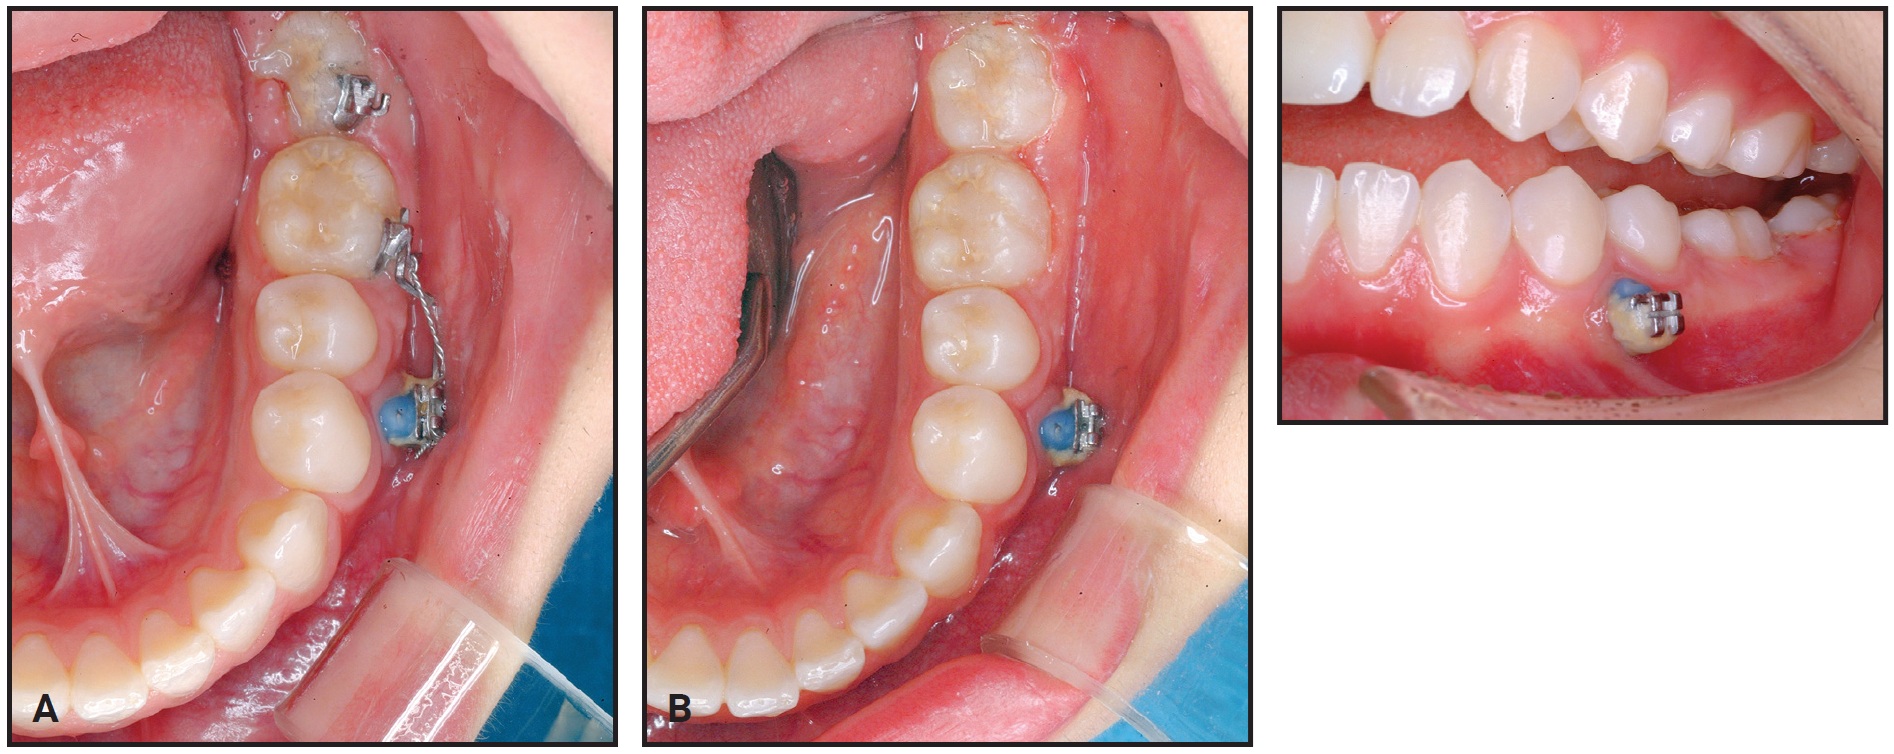

After 20 months of treatment, most of the lower right first-molar space had been closed by the mesial movement of the second molar. A gingival cleft had developed as a result of soft-tissue folding, and bone loss on the mesial side of the lower right second molar was evident on a panoramic radiograph at 24 months (Fig. 10).

Fig. 10 Case 2. A. Gingival cleft caused by soft-tissue folding after 24 months of treatment, with bone loss apparent on mesial side of lower right second molar. B. Gingival cleft evident in interproximal area of second premolar and protracted second molar. C. Illustration of gingival cleft caused by closure of edentulous space.

Total treatment time was 27 months (Fig. 11). The post-treatment records showed the gingival cleft between the second premolar and the protracted second molar, bone resorption in the mesial part of the second molar, and apical root resorption of the protracted second molar. In addition, bone atrophy in the buccolingual dimension was observed in the bone between the second premolar and the second molar.

Fig. 11 Case 2. Patient after 27 months of treatment.

In Case 1, no alveolar bone resorption or buccolingual alveolar bone atrophy was seen. On the other hand, in Case 2, where the entire first molar was extracted before treatment, we observed buccolingual alveolar bone atrophy and resorption of anterior alveolar bone, as well as more periapical resorption of the protracted second molar.

The overlying soft tissue on the edentulous ridge eventually matures after molar extraction. Because soft tissue remodels more slowly than the bone does, this mature soft tissue may fold down and produce a soft-tissue cleft during space closure (Fig. 10C). In Case 1, the presence of the mesial root prevented soft-tissue maturation and may thus have reduced the risk of developing a soft-tissue cleft. In Case 2, the soft-tissue folding caused bone resorption, which can be accelerated when a patient has poor oral hygiene.14 If a large edentulous space is involved, guided bone regeneration should be considered to prevent such bone resorption.6 A preventive gingival graft or apically repositioned flap can be considered ahead of space closure, or the folded soft tissue can be removed.